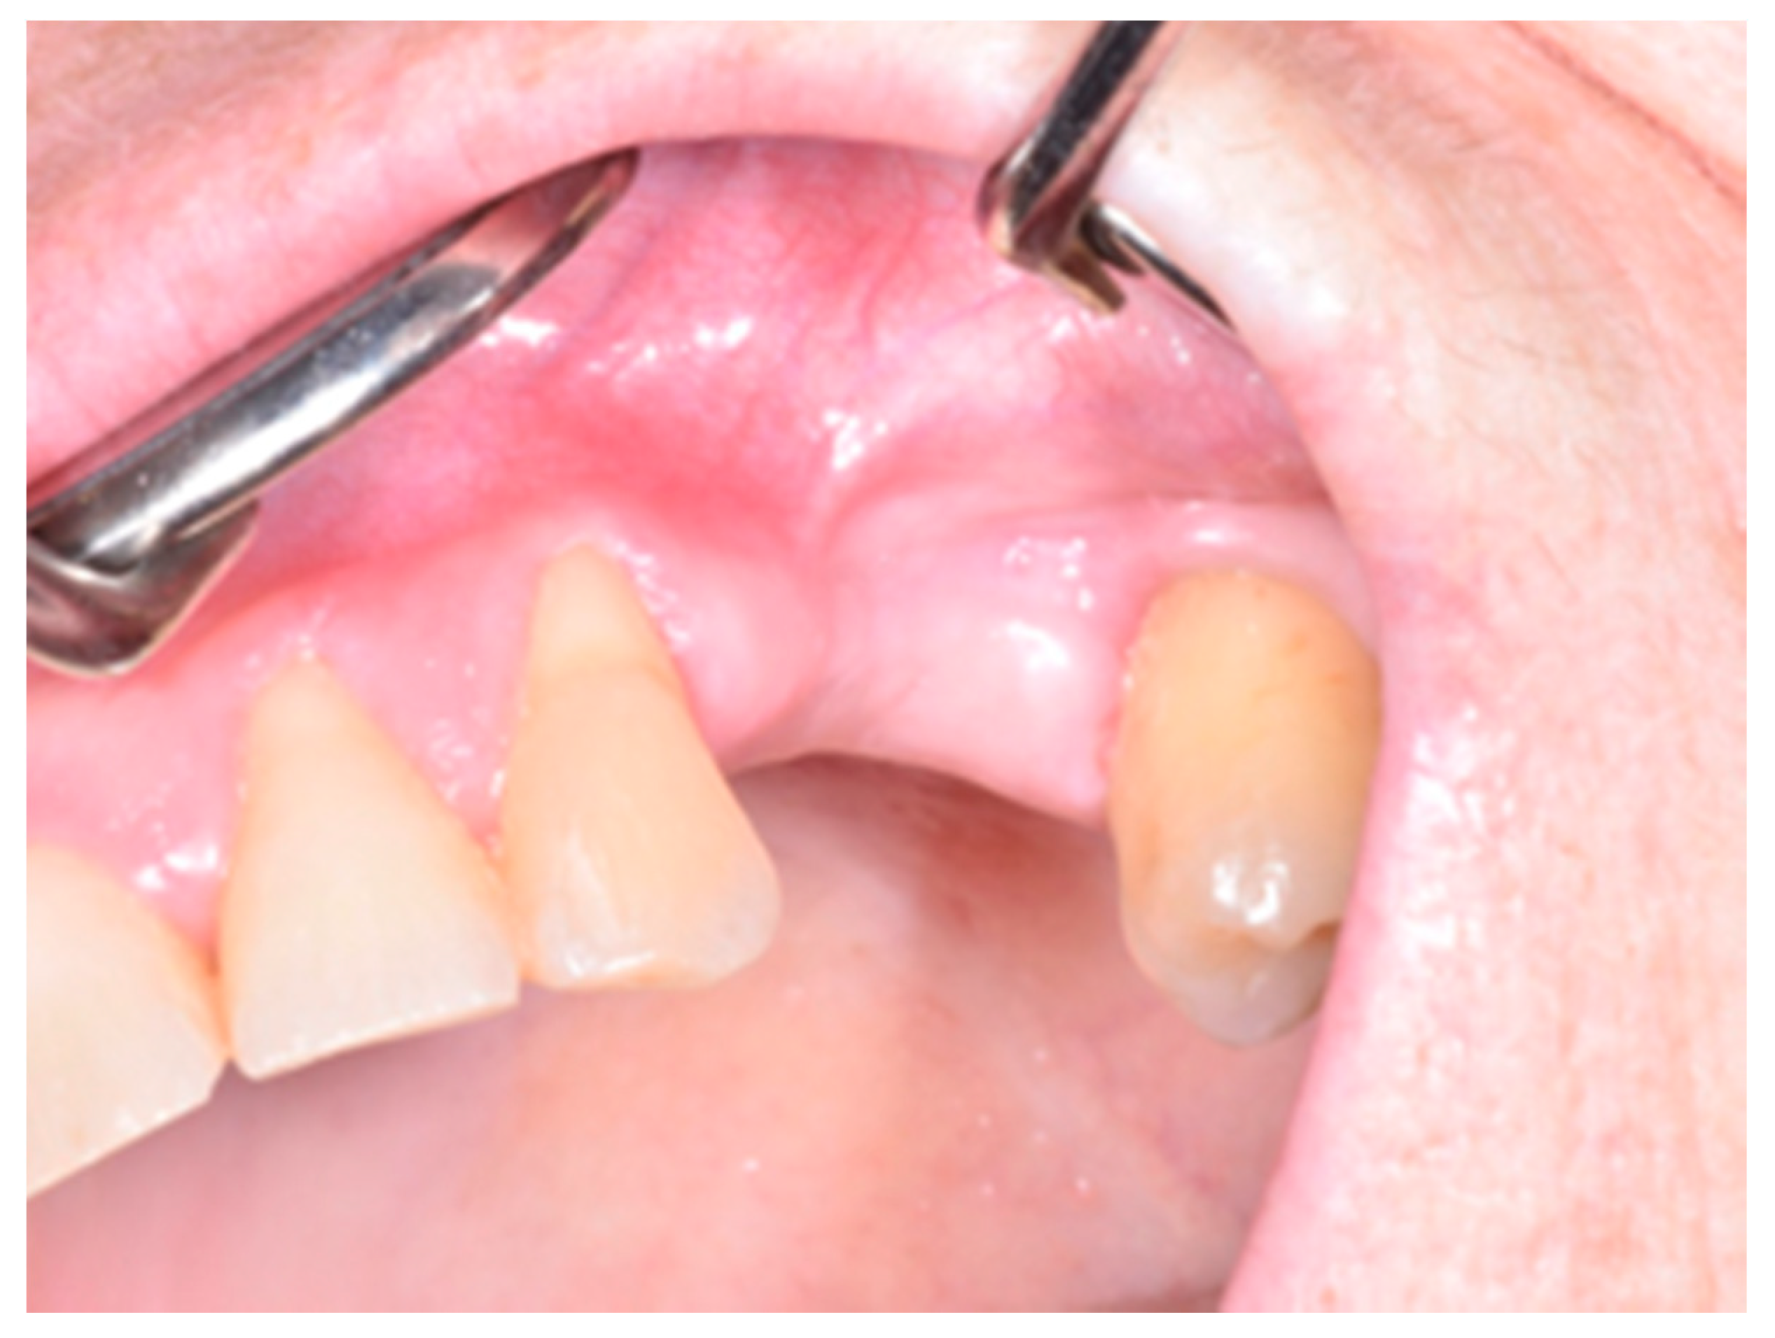

2. Materials and Methods

3. Results

4. Discussion